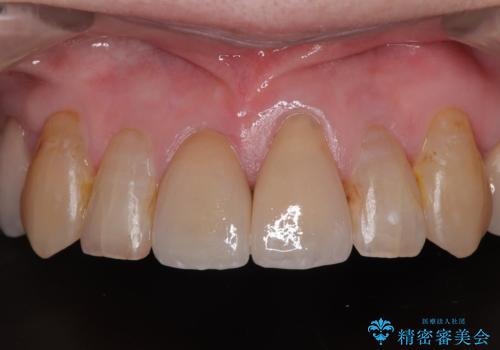

歯肉移植などによる前歯部の歯肉ライン改善を提案しましたが、口を開けたときにほとんど見えないので気にならないとのことで、特に処置を行うことなく補綴治療を行いました。